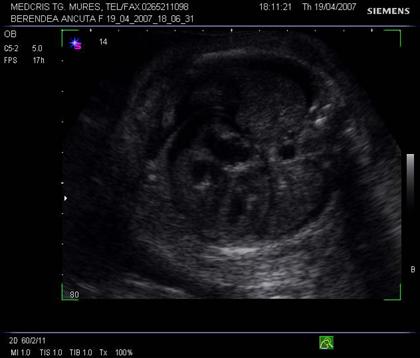

Fig. nr. 242. Aceeati sarcina ca in figura precedenta, se remarca lichidul pericardic si bilateral cel pleural, in sectiune transversala la nivel toracic fetal.